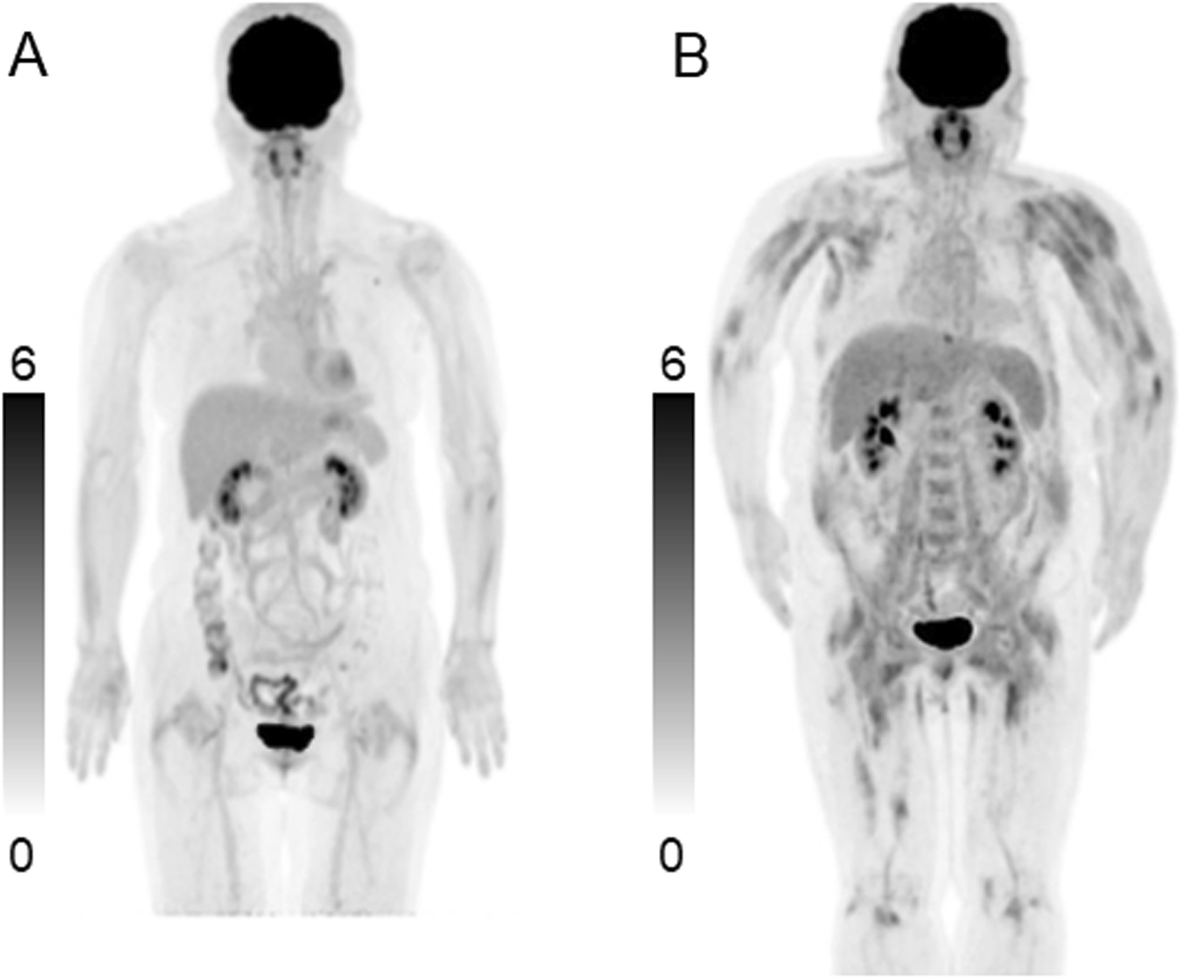

18F-FDG PET/CT in patients with polymyositis/dermatomyositis: correlation with serum muscle enzymes | EJNMMI Reports